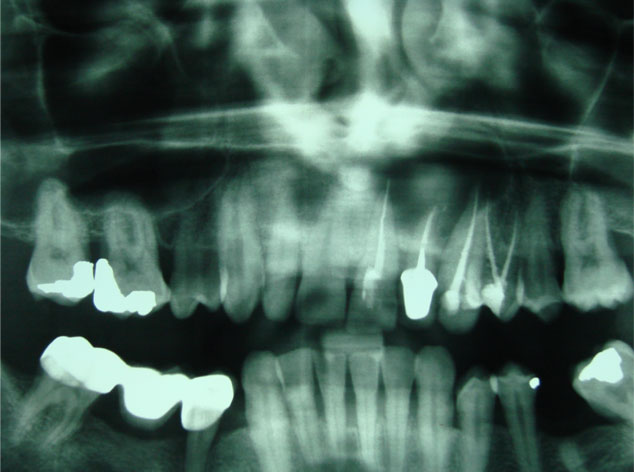

Aunque su estirpe anatomopatológica sea benigna, son quistes que en algunos pacientes provocan grandes destrucciones maxilares, porque crecen de forma asintomática durante años.